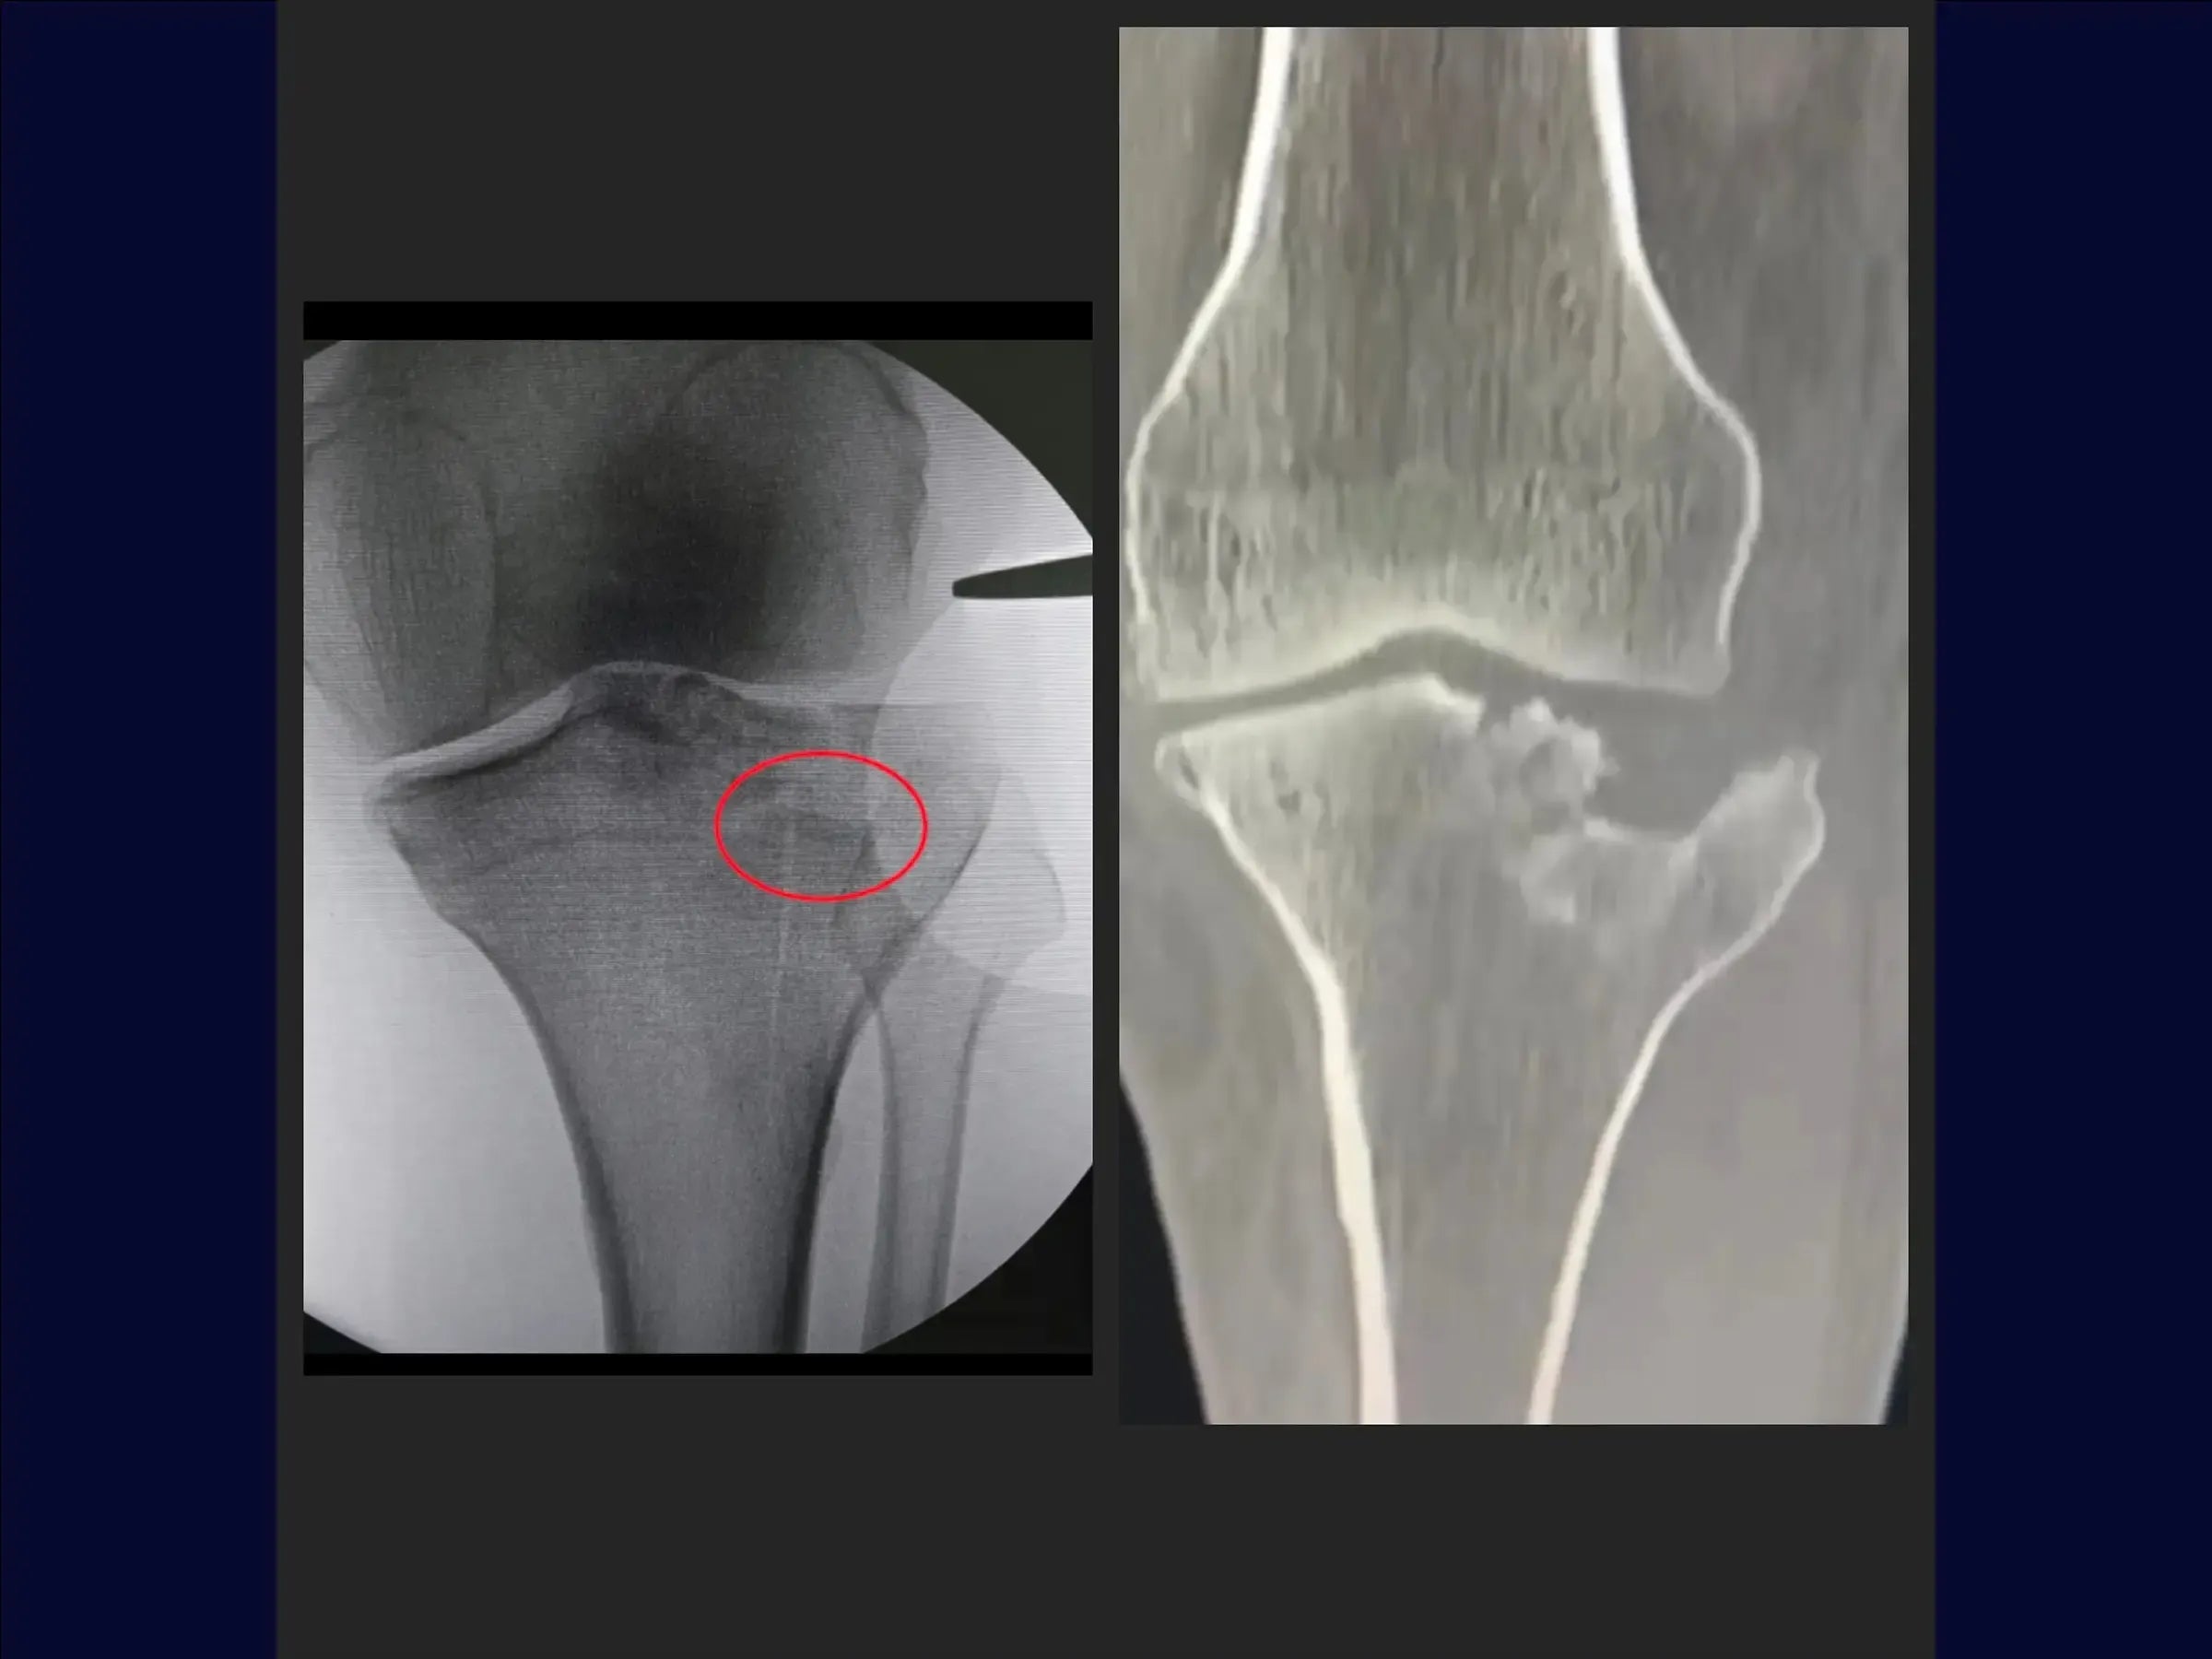

Fratura do Platô Tibial com Afundamento Central (Acesso Anterolateral e Osteotomia Incompleta)

Domine o tratamento de fraturas do platô tibial com afundamento central. Este treinamento oferece uma imersão técnica na osteossíntese utilizando osteotomia incompleta e acesso anterolateral específico, apresentado em vídeo 4K sob a perspectiva cirúrgica, para restaurar a anatomia e a função articular.

- Osteossíntese de fraturas do platô tibial com afundamento central e cisalhamento incompleto.

- Osteotomia Elástica para Redução Anatômica: Abordagem de osteotomia incompleta que mantém a cortical anterolateral íntegra, permitindo o levantamento do fragmento afundado com retorno natural à posição.